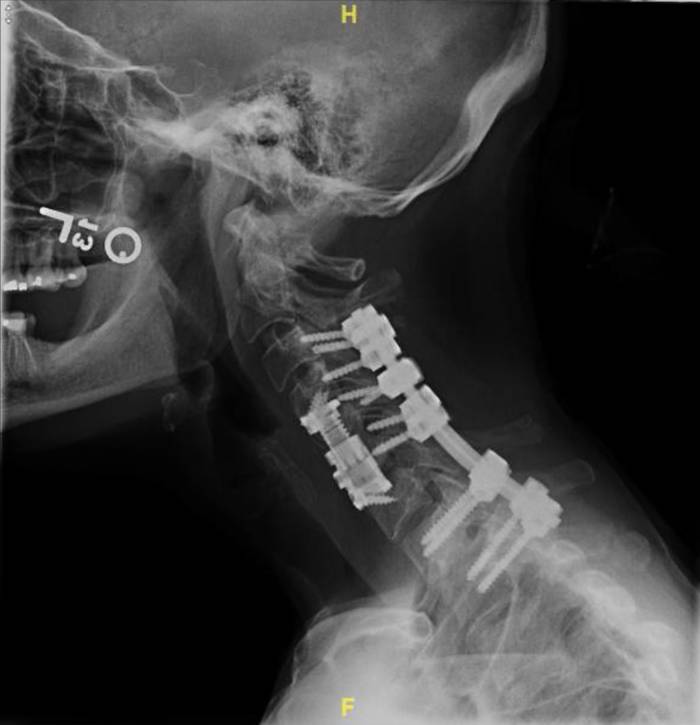

For both the lateral and the AP views, there are two separate sources of motion that could contribute to differences between the “pre” and “post” images: movement of the patient and the ovement of the spine and/or screws. The camera itself has preset positions for both views, with millimeter-level noise between separate images that can be effectively ignored. As the movements of the patient are extraneous, they introduce noise that makes it difficult to evaluate patient progress and diagnose any potential issues (e.g. pseudarthrosis) that may cause major health risks. As a result, a patient that may come in after their operation to diagnose why they haven’t seen the expected improvement may require additional x-rays which delay the process, which could result in any medical conditions worsening or potentially another operation being required.

We will create an algorithm enabling users to upload both the “pre” and “post” images, realign/manipulate them, and eliminate noise induced by movement of the patient. By doing so, the lab will be able to make more accurate diagnoses and prognoses of their patients. Having specific, quantitative data on the relative positions and movements of screws and vertebral bodies of interest would help patients to make the best of their own and the lab’s time and diagnose any complications earlier for better health and less cost to the patient.